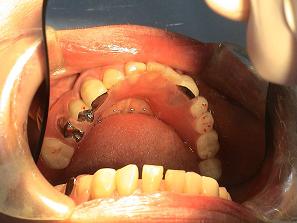

2. 作製したバネなし入れ歯

(バルプラスト)です